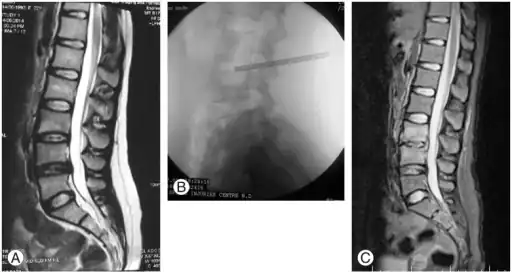

- MRI